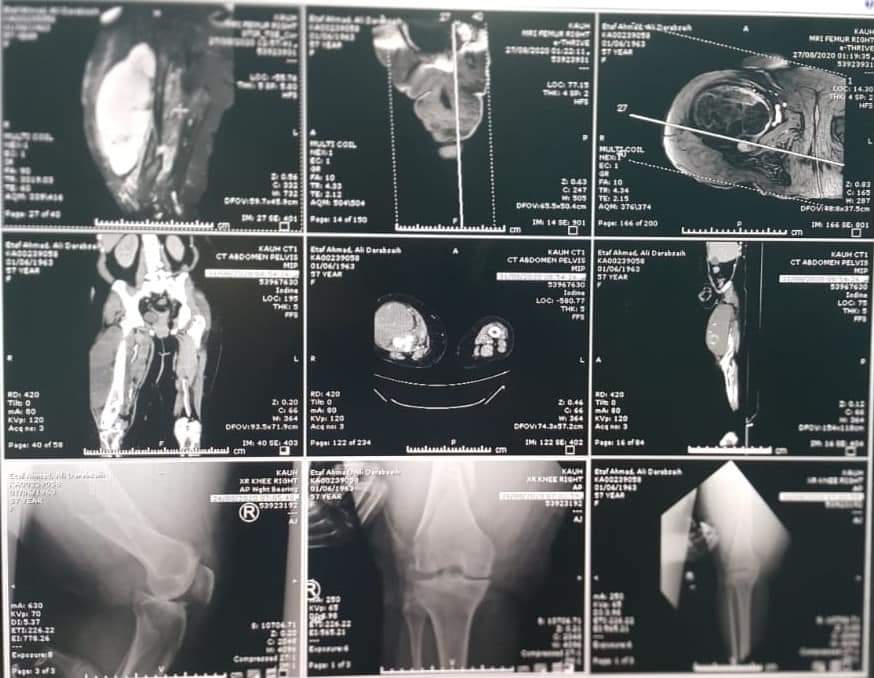

حيث تمكن قسم الجراحة الخاصة / شعبة العظام في المستشفى من إجراء عملية نوعية لمريض يعاني من وجود ورم رخوي خبيث ضخم في الفخذ الايمن بالاضافه لتعرضه لكسر في عظمه الفخذ .

وأجرى العملية فريق طبي بإشراف إستشاري جراحة أورام العظام الدكتور زياد مهيدات حيث استغرقت العملية الجراحية (6) ساعات وتعتبر هذه العملية من العمليات المعقدة والصعبة ،حيث أظهرت الأشعة ضخامة الورم وقربه الشديد من الاوعية الدموية والاعصاب الرئيسية المغذية للساق .

وأشار الدكتور مهيدات إلى أن معاناة المريضه تمثلت بوجود هذا الورم الخبيث الضخم بالاضافه لتعرضه لكسر اثناء فتره العلاج الكيماوي الذي كان بأشراف أخصائي باطني أمراض الدم والاورام الدكتور عدنان سعد ما قبل تجهيزه لعمليه ازالة الورم، حيث اظهرت نتيجه الخزعه للكتله المستأصله خلو حوافها من الخلايا السرطانية، وبذلك كان تقرير الخزعه هو استئصال كامل الورم بحمد الله" مبيناً إن هذه العمليات يجريها بالعادة فريق جراحين متخصصين في مراكز متخصصة مثل هذا المركز الجامعي المميز والمجهز بأحدث الأجهزة والذي يشهد تقدماً كبيراً ، وثمن دور الكادر الطبي الذي شارك في العملية؛ الدكتور عبد الكريم صنع الله، الدكتور حمزه بني يونس ،الدكتور مقدام البياتي والدكتور حمزة الضميدات وأطباء التخدير برئاسة استشاري التخدير الدكتور ذياب بني هاني وكادره الطبي الدكتور اسماعيل ابو الشعر والدكتور سيف الغرايبه والكادر التمريضي المميز م.ق محمد الغزو، م.ق ظاهر ربضي، م.ق محمد الدلكي، م.ق نضال عموش وبوجود فنيين تخدير واشعه مميزين .